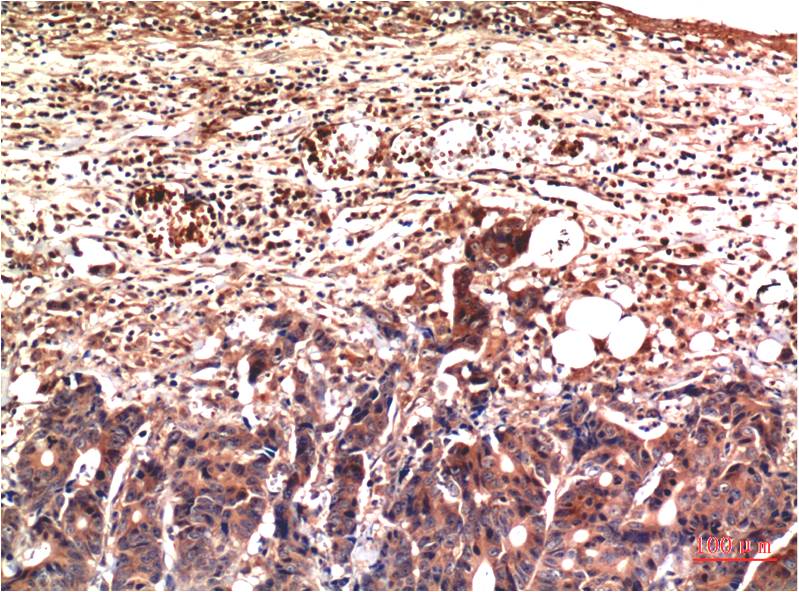

• Immunohistochemistry analysis of paraffin-embedded Human Stomach Carcinoma Tissue using Ubiquitin antibody. High-pressure and temperature Sodium Citrate pH 6.0 was used for antigen retrieval.